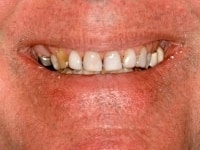

Case Details

Implant used to replace a single missing tooth, note the healthy gums and nice appearance of the implant crown

View Angle: right-front-oblique

Before

After